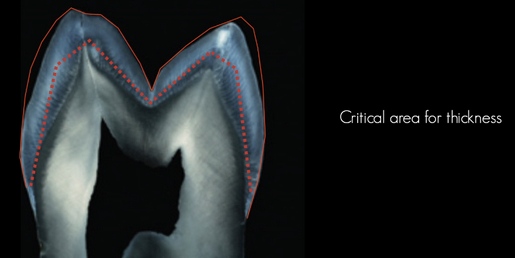

14- Thickness and Material Of The Crowns